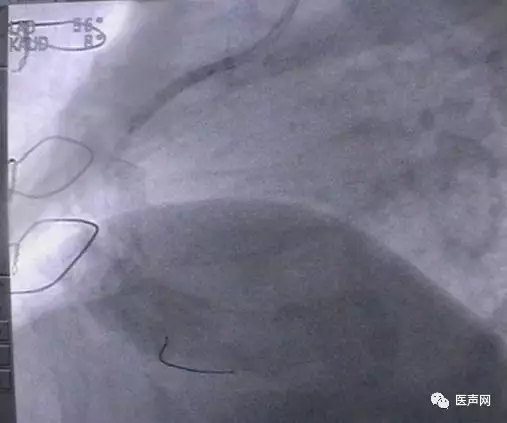

病例3:LAD中段90%狭窄

操作过程:JL4导引导管同轴性不好,支撑力不够,直接支架术(direct stent)有阻力,改用EBU 导引导管---植入TAXCOR 3.0×18mm DES.说明:导引导管的重要性。下图所示: